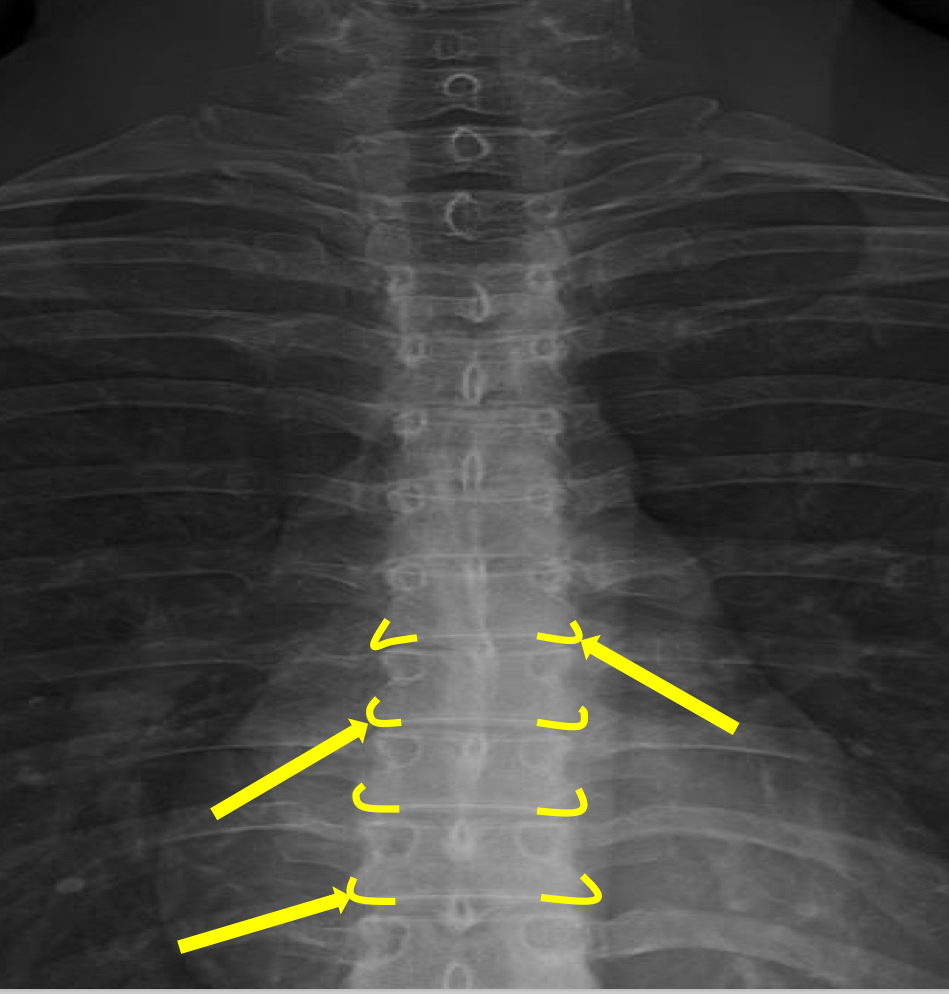

What view is this?

AP (Anterior to Posterior) Thoracic

What is this?

Junction of Laminae

What is this?

Pedicle Shadows

What is this?

Vertebral Waist

What is this?

Inferior Endplate Tips

What is this?

Superior Endplate Tips

What is this?

Disc Spaces